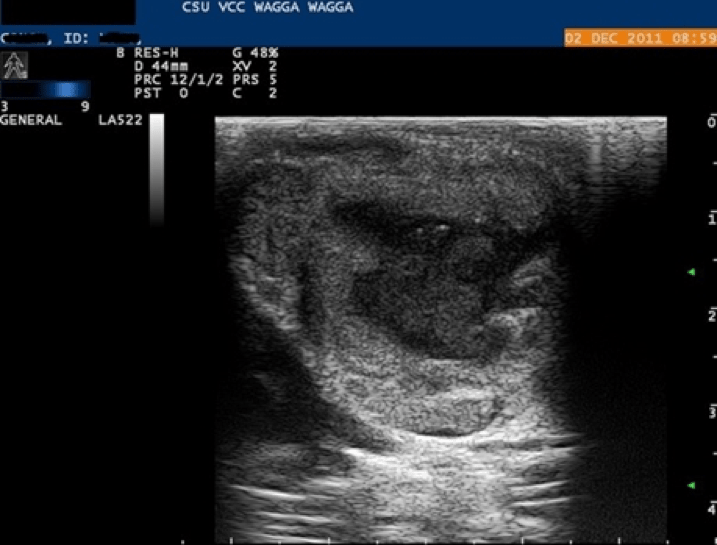

You perform an ultrasonographic examination of the lymph nodes: